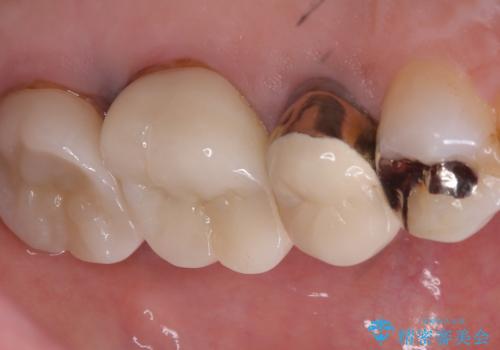

【セラミッククラウン】土台と被せものがズレている気がする

- 主訴:いつも物が詰まる場所があり気になる。衛生士に被せものと土台の境目に汚れが溜まっている箇所があると指摘され気になっている。

過去に入れた被せものと土台の歯との適合が悪く、隙間が出来ておりそこに汚れが溜まりやすい状態になっていました。セラミッククラウンでのやり替えとなりました。

唇側マージン不適なこと説明し、審美性・適合性に優れたセラミッククラウン(スタンダード)でのやり替えとなりました。